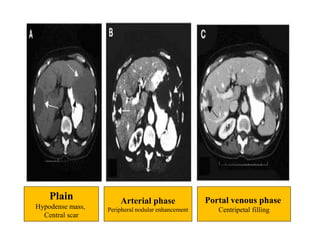

Plain

Hypodense mass,

Central scar

Arterial phase

Peripheral nodular enhancement

Portal venous phase

Centripetal filling